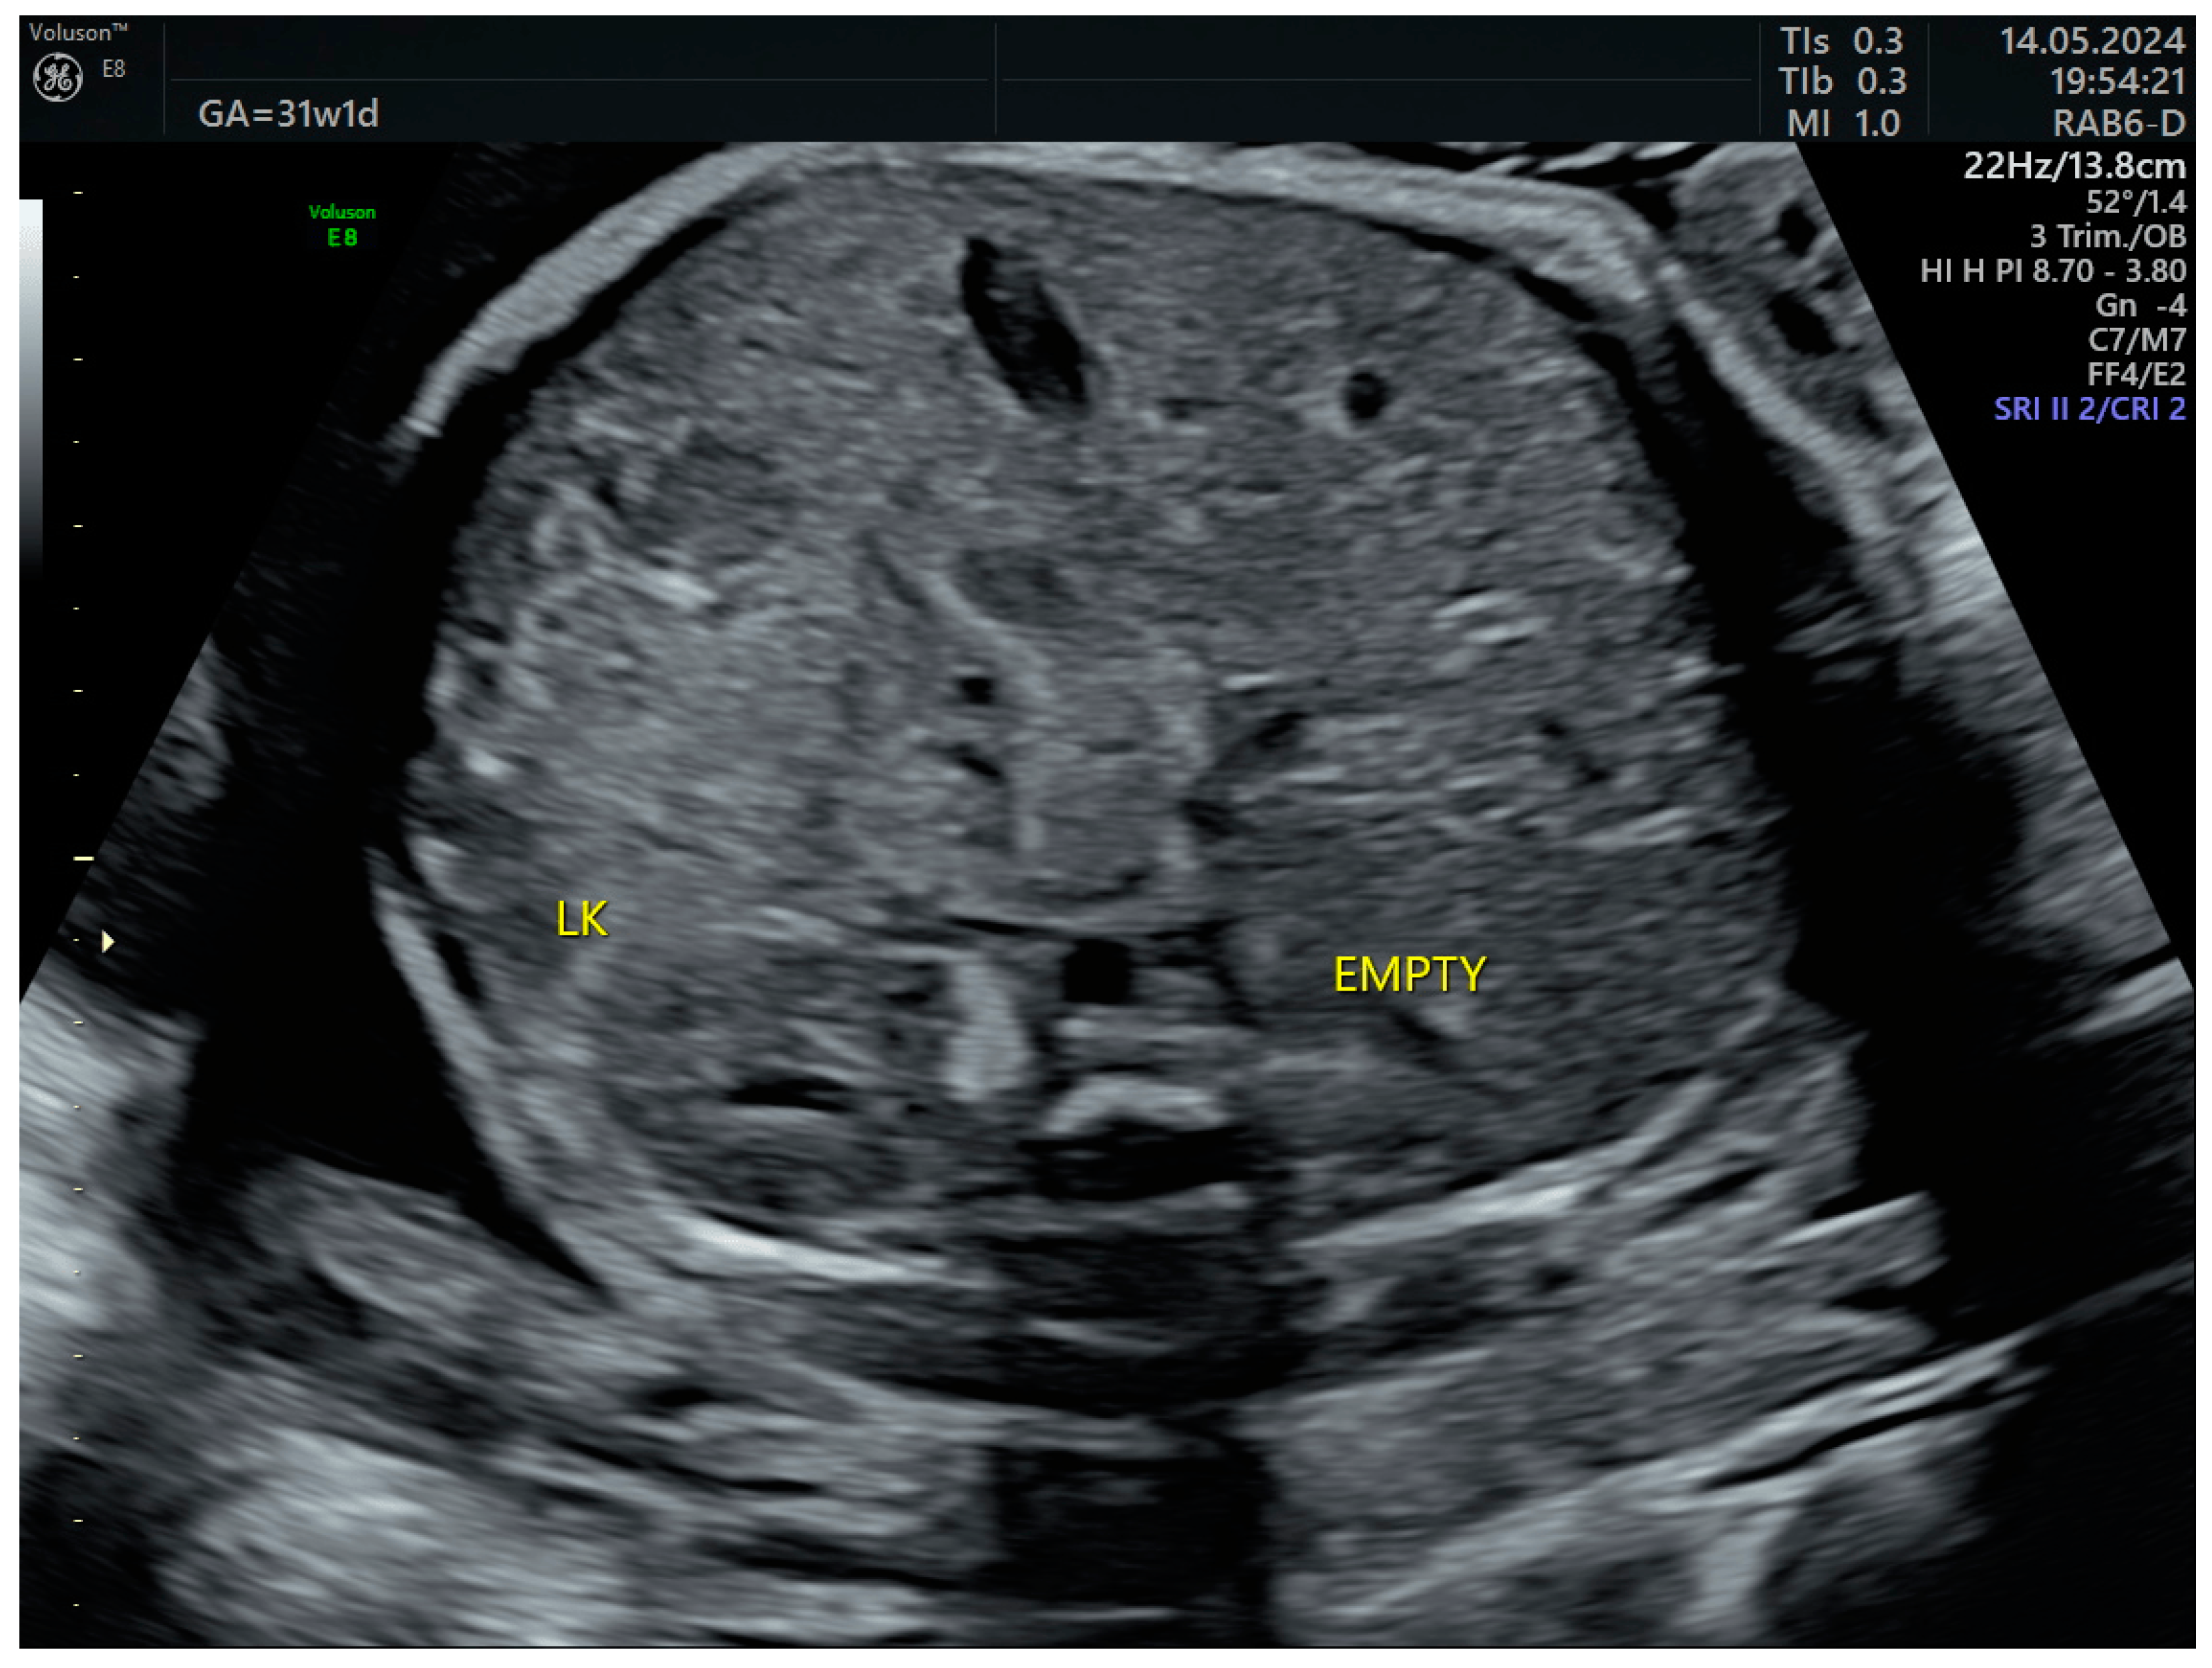

The third-trimester ultrasound evaluation at 31 weeks and 5 days confirmed once again the presence of crossed fused renal ectopia. Although the frequency of the associated changes (hydronephrosis, calyceal dilatations, ureteral dilatations, ureterocele, oligohydramnios, vesicoureteral reflux, etc.) in the third trimester is relatively high, none of these complications were present at the time of examination (Figure 7 and Figure 8). No other anomalies or deviations from the fetal growth curve were recorded, even though, starting from the 28th week, the patient developed diet-controlled gestational diabetes. The final diagnosis was isolated crossed fused renal ectopia.

Figure 7. Right lumbar fossa without renal image—third-trimester morphology scan at 31 weeks. LK—left kidney.